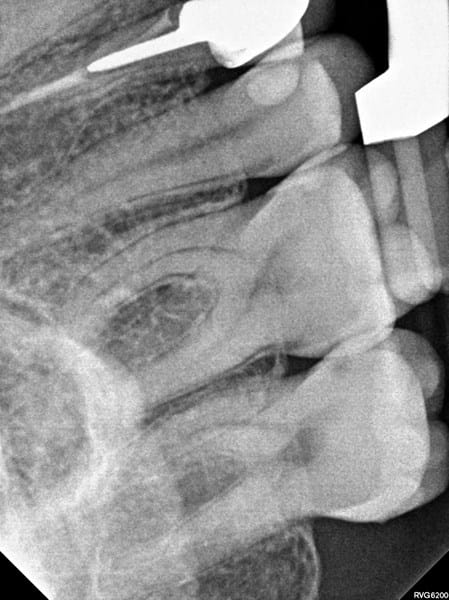

Extracción o re endodoncia, que es lo mejor? RX adjuntos

En julio de este año, me apareciò un absceso sobre el diente (corona), que fue tratado con antibiotico (amoxicilina) y la infección se fue, pero luego de unos meses esta infección volvió consultè a un dentista que decide que hay que extraer la pieza dental y realizar un implante, posteriormente consulté otro dentista que recomienda, realizar el tratamiento conducto nuevamente y colocar corona nueva, o bien realizar un procedimiento desde afuera para re limpiar el canal, porque dice que el conducto esta bueno, y es una parte de nervio que quedó porque la endodoncia quedo mal hecha desde un principio.

Desde la infección esa parte de mis encia sangra y actualmente siento un mal sabor y olor en la pieza dental cuando paso el hilo dental.

Adjunto los rayos X